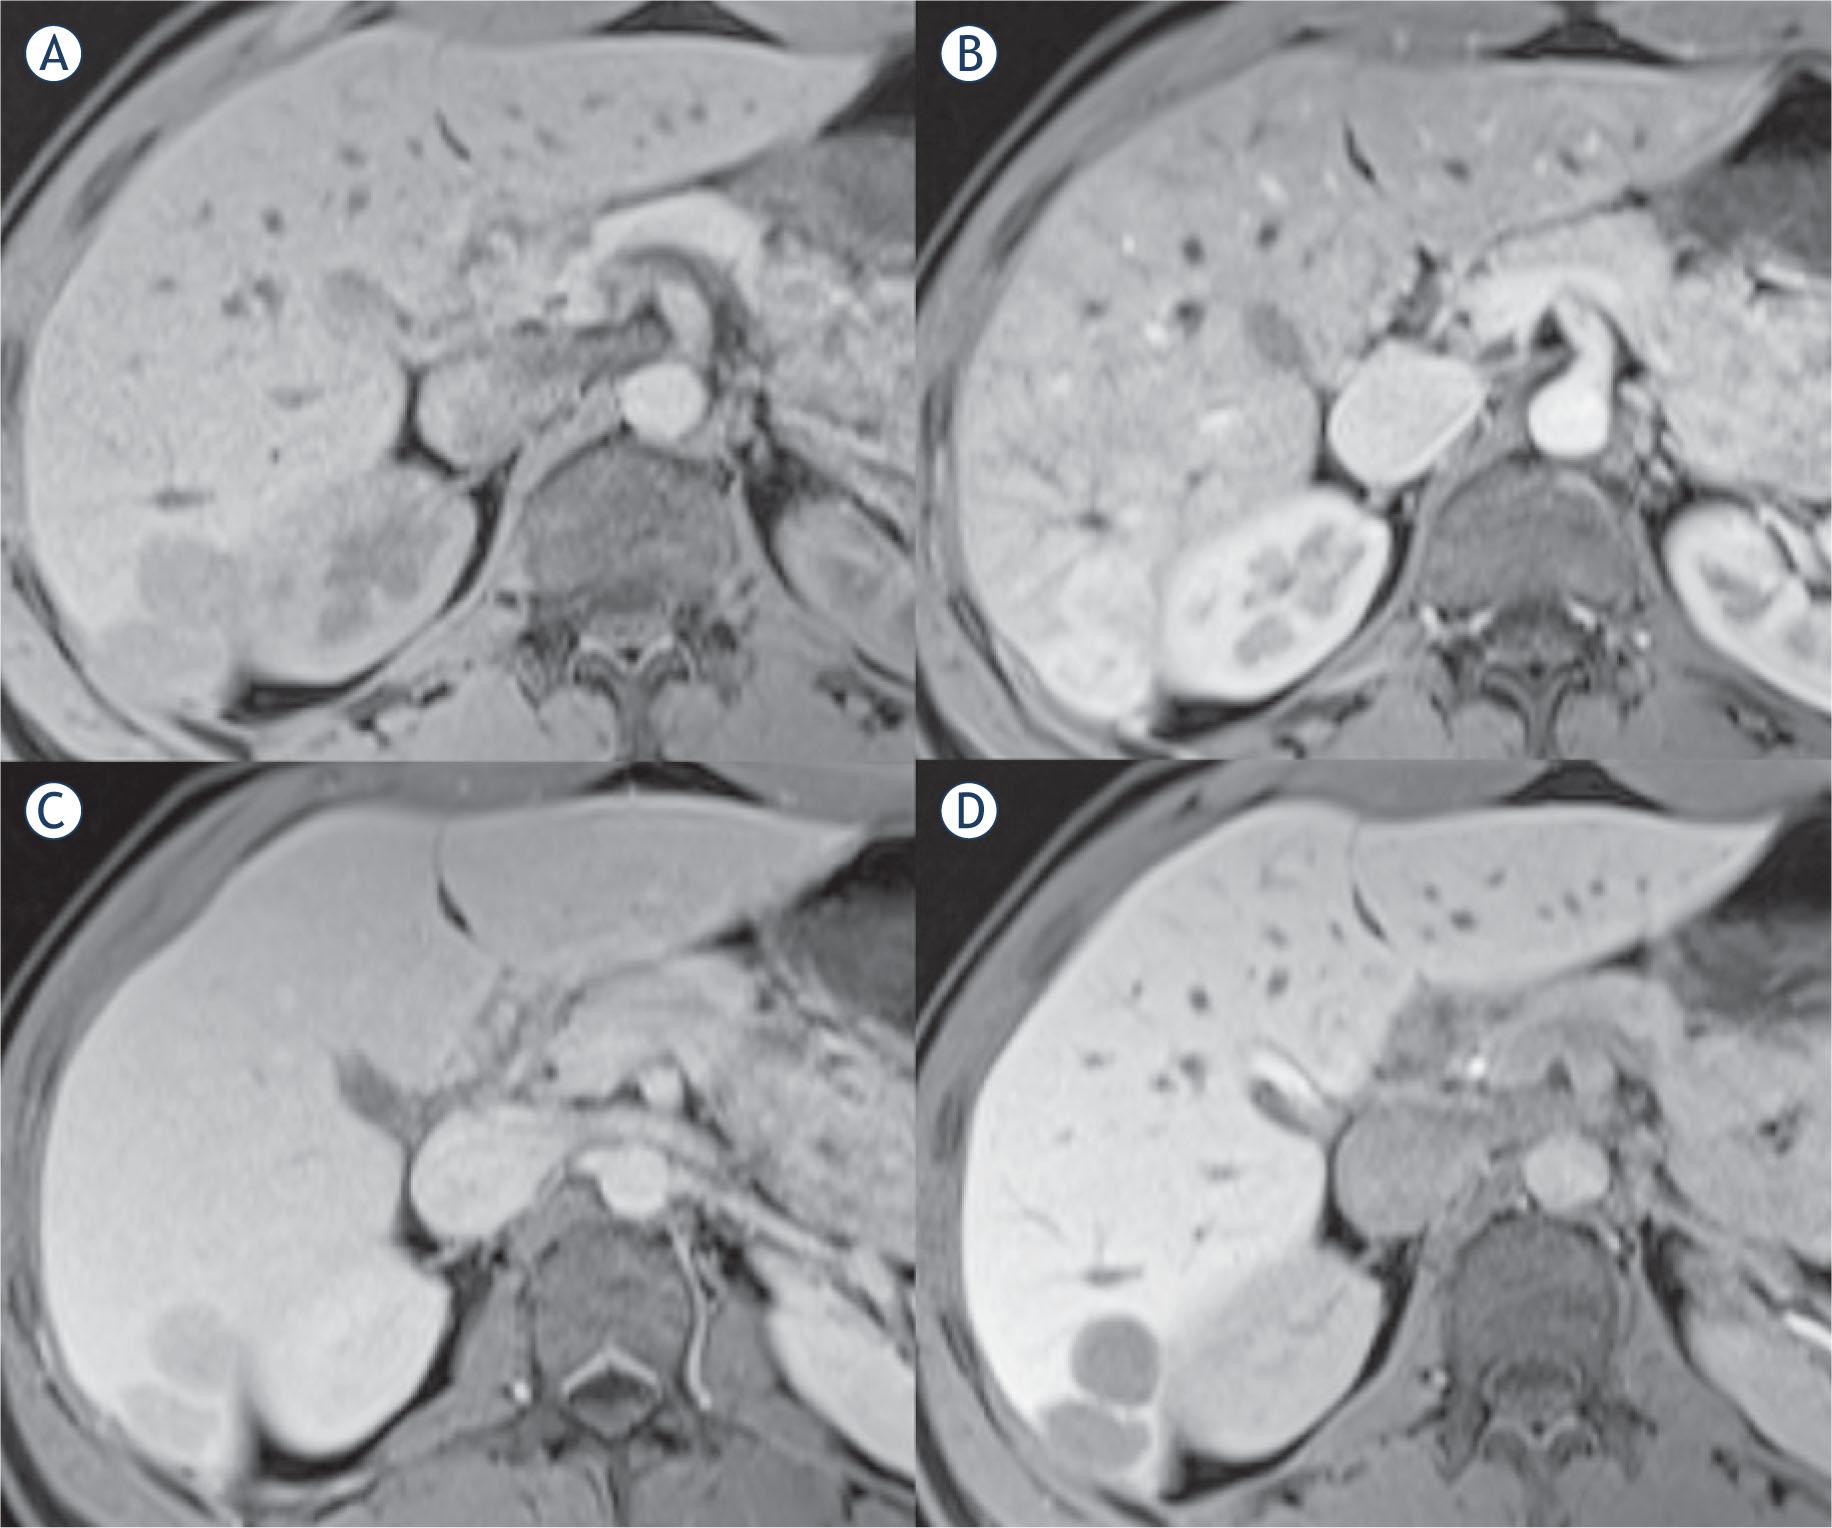

MRI; hepatic lesions in T1 volume interpolated breathhold examination (VIBE) fat saturated (FS); (A) pre-contrast; (B)arterial phase; (C) portal phase; (D) delayed phase (20 minutes) of enhancement.